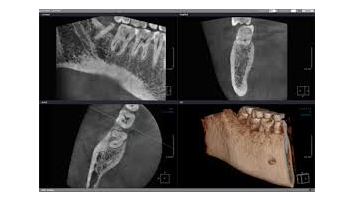

Autrement, du fait de la précision qu’il apporte, le cone beam reste un examen de choix en implantologie. Il permet d’évaluer au plus juste le volume osseux et la position des structures anatomiques délicates comme les nerfs en vue de la pose d’implants. La modélisation en 3D permet en outre de choisir la taille et la forme des implants proportionnellement à la morphologie du patient et de simuler leurs emplacements virtuellement.